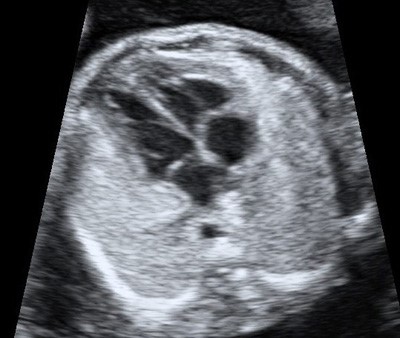

Камеры сердца плода на 22-й неделе беременности в режиме 2D